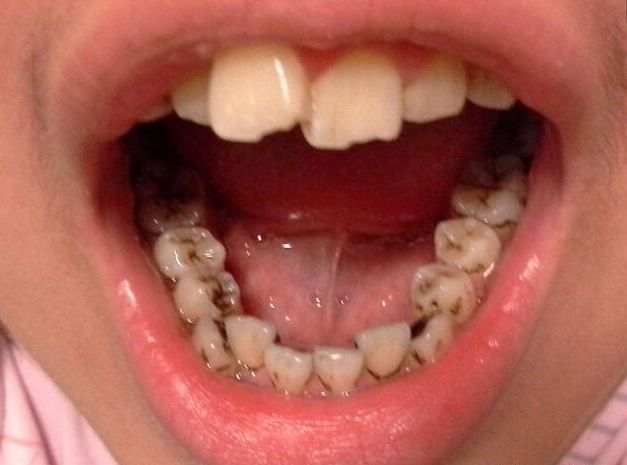

02 牙面有黑点

牙齿表面有黑褐色改变,或有失去光泽的白垩色斑点,或两牙相邻处有变暗的黑晕,这些都是虫牙的早期表现,需尽早治疗,以免牙洞越来越大,伤害到牙神经。